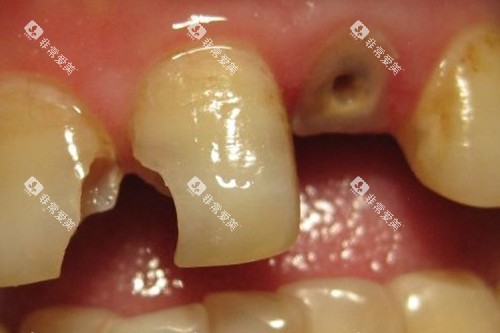

特别是初诊时,医生会进行超全细致的口腔检查,用可靠相机拍摄口腔内照片,直观地向患者展示牙齿状况,帮助理解治疗方案。